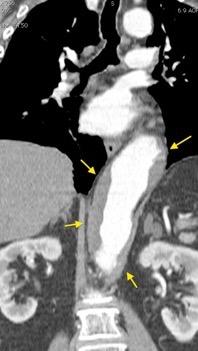

Diafragma “colgante” (“dangling sign”)

(“Dangling sign”)

TC. Mejor con multicorte. (reconstrucciones).

Asociación: Aire en pared.

Fracturas costal .Rotura esplénica. Neumoperitoneo.

Diafragma discontinúo Herniación de la grasa omental

Desser TS et al.The dangling diaphragm sign: sensitivity and comparison with existing CT signs of blunt traumatic diaphragmatic rupture. Emerg Radiol 2010